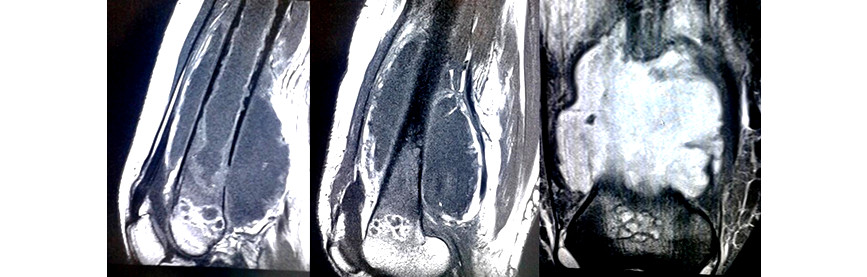

Se realizó resonancia magnética nuclear (RMN) del muslo derecho (Fig. 4). Se detectó una masa de aspecto heterogéneo, de 8 x 9 x 19 cm, contornos irregulares. En las secuencias sagital y coronal se observaron hipointensidad en T1 e hiperdensidad en T2 localizada predominantemente en el tercio distal del muslo, con invasión del canal medular e infiltración de los grupos musculares anteriores y posteriores del muslo, desplazamiento de la arteria femoral y compresión del sistema venoso profundo, asociada con osteolisis y periostitis.